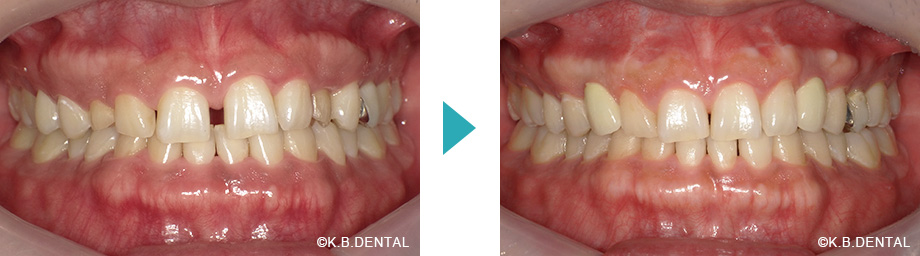

叢生・反対咬合の症例

| 主訴 | 上下の歯並びが気になる。受け口を治したい。 |

|---|---|

| 診断名 | 反対咬合 |

| 初診時年齢/性別 | 40歳女性 |

| 装置 | マウスピース矯正(インビザラインGo) |

| 抜歯/非抜歯 | 非抜歯 |

| 治療期間 | 約1年半 |

| 費用 | 68万円(税別) |

| リスク副作用等 | 矯正歯科治療のリスク副作用について |